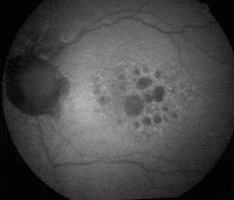

Central Vision Analyzer GIF